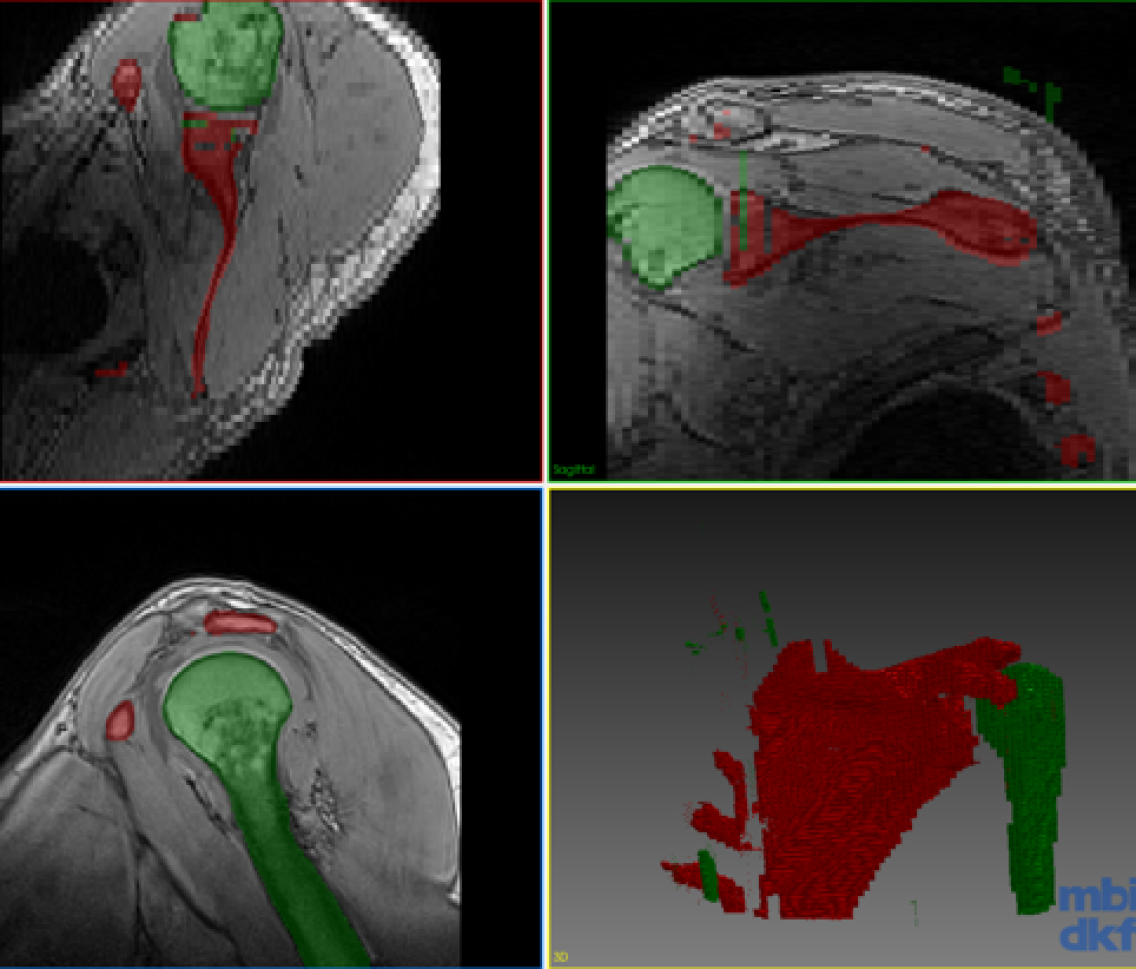

Refer to caption

(e) LwfSeg Case 3

(f) CoRiSeg Case 3

Figure 3: Segmentation of the test volume with different methods.

Our experimental dataset consists of 9 Dixon sequences of left shoulder collected with 1.5 Tesla at resolution of 0.91 mm x 0.91 mm x 3 mm, corresponding to 192x192x64 voxel resolution. Humerus and scapula bones were annotated by an expert. Our goal is to combine knowledge from different data for a network that can segment both anatomical structures. We evaluated our proposed method for the three scenarios shown in the table in Fig. 2. One volume each was fixed randomly for validation and testing each of all scenarios. The first scenario (Case 1) tests a typical setting where different anatomies were of interest and thus annotated in separate studies. The second scenario (Case 2) aims to observe advantages of incremental training with minimal effort, i.e., incrementally annotated data, giving insight on an extreme case where a single volume annotation is provided. The last scenario (Case 3) studies the feasibility of combining learned segmentation information from different anatomy and images of different contrast. The methods were implemented with Tensorflow [14] and ran on an Nvidia Titan X GPU. Proposed network is implemented in 2D, hence 646464 image samples per volume given in Fig. 2. For a fair comparison, we fixed all parameters across different models to kcsubscript𝑘𝑐k_{c}==505050, krsubscript𝑘𝑟k_{r}==303030, α𝛼\alpha==0.50.50.5, tMCsubscript𝑡MCt_{\mathrm{MC}}==292929, batch size of 8 images, and trained all models for 1000 epochs. Used network (cf. Fig.1) has a first convolutional layer with 64 filters and the amount of filters double at every coarsening level. Each convolutional layer is proceeded with a batch normalization and ReLU activation. For CoRiSeg, we use a VGG16 network [7] pre-trained on ImageNet [13]. While a VGG trained on a medical image set would be expected to provide more accurate dcontsubscript𝑑contd_{\mathrm{cont}} score, training set of ImageNet is not matchable by any annotated medical database. We used Dice similarity coefficient and average symmetric surface distance for evaluating segmentation performance across tested methods (cf. Table 1). We compared our proposed methods: LwfSeg with its extensions with exemplar sets AeiSeg and CoRiSeg. Upper bound cases are presented with networks trained on only a given anatomy/dataset, i.e., without any incremental learning and hence without the need to preserve “old” (extra) information. We also show results from finetuning for comparison, although catastrophic forgetting is a known problem. In Fig. 3, we showcase qualitative results from different scenarios (cf. table in Fig. 2).

As seen, with finetuning, the shared network body gets re-tuned to adapt to the new incremental data, almost completely forgetting the initial classes. Proposed segmentation extension of learning without forgetting (LwfSeg) performs relatively well in all cases. For every scenario, both proposed methods using exemplar sets either outperform or achieve performance as close to LwfSeg for the old class. CoRiSeg achieves the highest Dice score for the old data, suggesting that for selecting exemplars the maximum set coverage over content distance is more effective than averaging at abstraction-layer (AeiSeg). In addition, in Case 2, where the incremental dataset is severely handicapped, both LwfSeg and CoRiSeg surprisingly outperform HumSeg. While it is expected for a network trained on 1 volume (64 images) to perform poorly, incremental networks are seen to achieve higher segmentation performance, suggesting that shared-body layers potentially learned to extract bone-generic knowledge. Should this be shown for a wider range of bone structures, it would be critically relevant for orthopedic applications in the future. When the incremental dataset is introduced from a different imaging sequence in Case 3, one can see the great advantage of keeping exemplar samples; i.e., 28.8% increase in Dice score of CoRiSeg compared to LwfSeg. While the performance difference is less obvious for the new class, the change in old class scores suggests distillation loss to have provided false “guidance” on the new dataset with LwfSeg, i.e. trying to retain old class segmentation performance without any exemplar samples. Since finetuning does not need to remember the appearance of humerus (bone) in the other image modality, it outperforms with scapula in Case 3. We expected VGG trained for object classification (on ImageNet) to select better exemplar images for our task. Indeed, compared to CoRiSeg, using the UNet trained by us for dcontsubscript𝑑contd_{\mathrm{cont}} yielded 1.6%, 0.7%, and 0.07% worse Dice, respectively, for each Case.

Note the high average symmetric surface distance in some of the proposed incremental methods, i.e., AeiSeg and CoRiSeg in Case 2; LwfSeg in Case 3. These are due to small blobs of false positives far from the target anatomy (cf. Fig. 3). These blobs could possibly be removed with a trivial post processing step (e.g. morphological operations, largest connected region, conditional random fields, user input), which is beyond the objective of this paper. Additional randomized hold-out test sets for Case 3 showed little variation (\approx2% Dice) in results, while the proposed AeiSeg and CoRiSeg were still over 27% Dice better than LwfSeg in retaining old class info. We will conduct extensive evaluations in future.